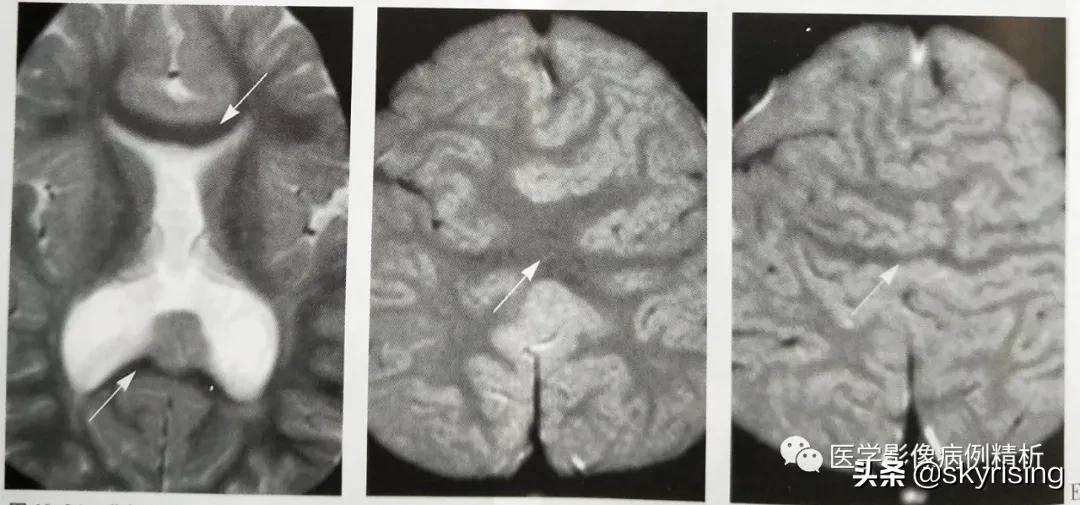

本型是前脑无裂畸形中发育最好、畸形最少的一个分型。双侧额叶靠近胼胝体嘴部和体前部部分实质融合,大脑前纵裂几乎完全存在,大脑镰发育不全,胼胝体前部发育不良,透明隔缺如,侧脑室额角发育正常或轻微变异,大脑后纵裂显示正常。如下图所示,双侧额叶部分脑实质融合,双侧额角略纤细,形态尚正常,注意短箭头所示大脑前动脉走行于前缘,本例偏于脑叶型和半脑叶型中间状态。